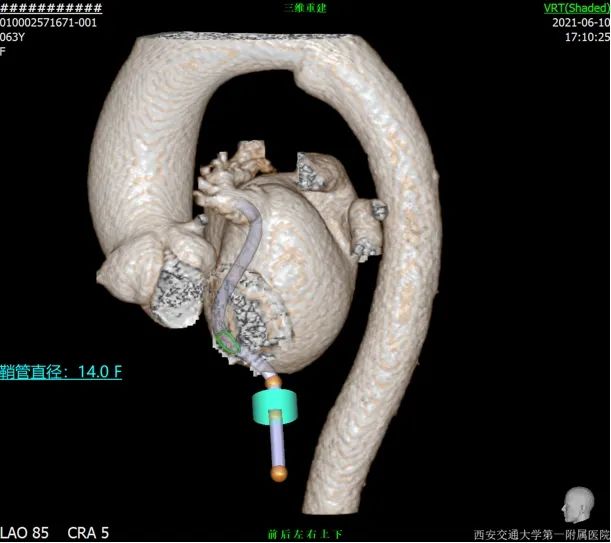

术前CT评估

行CT评估后左心耳内未见血栓,左心耳呈反鸡翅型,开口呈椭圆形,最短径17.3mm,最长径 21.7mm,三维深度19.1mm,二维深度 18.0mm。分析后提示宜选择24mm Watchman封堵器,但若采用下叶进行封堵,深度较浅,应首选上叶做为轴线进行封堵。

采用CT模拟最佳左心耳封堵工作体位,发现在RAO30 CAU25时左心耳展开较常规体位更好。

RAO30 CAU25

术前总结

患者TEE检查心耳内无血栓,TEE提示为反鸡翅可能,CTA重建心耳后为反鸡翅型,根据术前入路模拟,考虑穿刺点应偏下稍靠前,根据心脏CT及TEE评估结果来看,左心耳梳状肌发达,开口椭圆形,直径17mm-21mm,考虑24mm WATCHMAN封堵植入,在封堵轴线选择上应以上叶为首选。